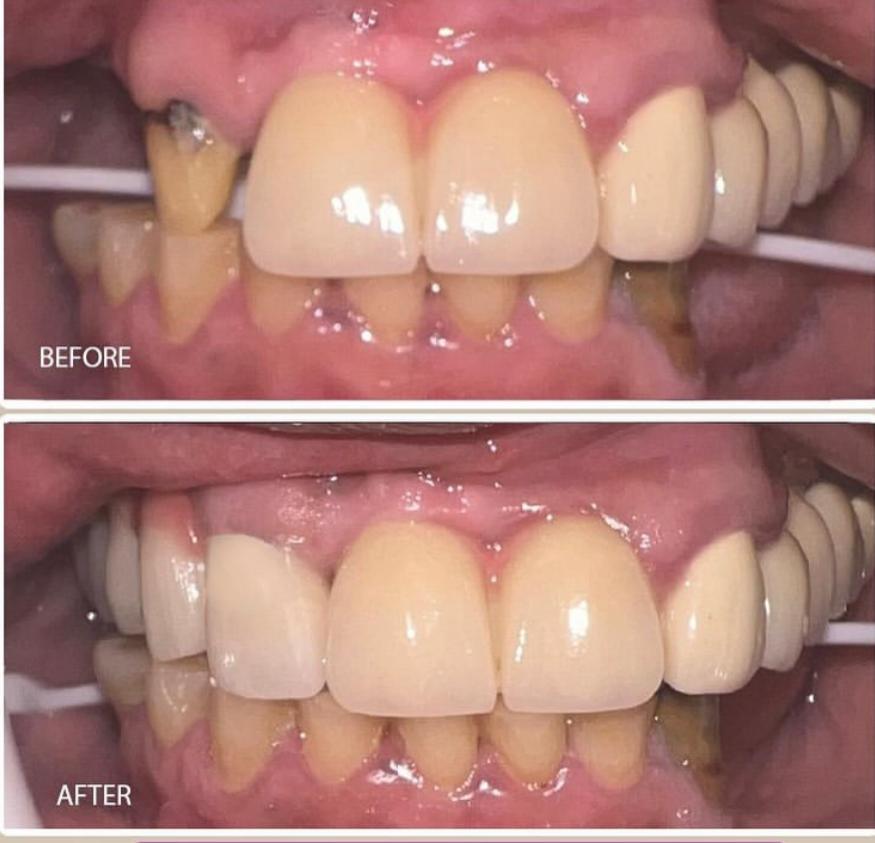

Dental Treatment Before and AfterClick To Enlarge White Teeth Lips Closeup Teeth Whitening Before After Teeth Whitening Transformation Before After Teeth Transformation Before After Man White Teeth Mustache Smile Teeth Whitening Transformation Before After Teeth Before After Transformation Teeth Before After Treatment Teeth Before After Composite Bonding Teeth Whitening Transformation Before After dental treatment dental treatment dental treatment dental treatment dental treatment dental treatment dental treatment dental treatment dental treatment dental treatment dental treatment dental treatment dental treatment dental treatment dental treatment dental treatment dental treatment dental treatment dental treatment